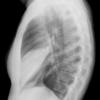

Case 3 RM & UL pneum Lat

Date: 07/04/2004

Views: 6791